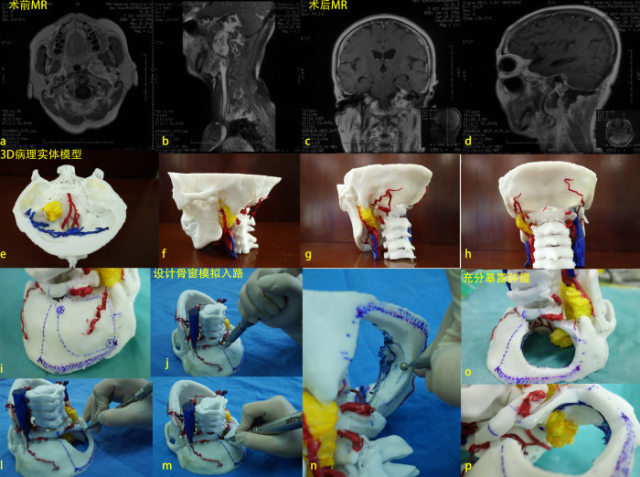

多融合容积成像技术弥补常规颅底外科手术术前预警、术中监测的缺陷,将全面的影像丰富至神经外科导航中,或是术前 3D 打印建立手术模型,完整的将肿瘤、颅神经、血管、骨质等模拟数字化影像与实际解剖结构之间建立动态联系,术中导航、术中核磁纠正病灶术中漂移,提高肿瘤的切除率,保护重要组织,减低并发症,实现颅底病变手术的精准化。

特别针对颅神经的三维重建,可以有效的在术中保护神经,减少患者术后面瘫、复视、面部麻木等多种并发症。

图片 5 复杂颅底肿瘤术前(3D 打印)计划